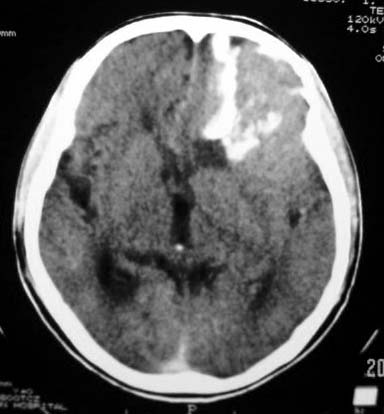

标题: CT7268:左额顶部病变增强片. [打印本页]

标题: CT7268:左额顶部病变增强片.

比较典型的少枝胶质细胞瘤ct表现,局部额骨垂直板有侵蚀变薄。

左侧额顶叶有条带状钙化的不规则形占位,增强呈不均匀轻度强化,局部颅骨受侵蚀变薄,典型的少支胶质细胞瘤。

比较典型的少枝胶质细胞瘤ct表现,局部额骨垂直板有侵蚀变薄